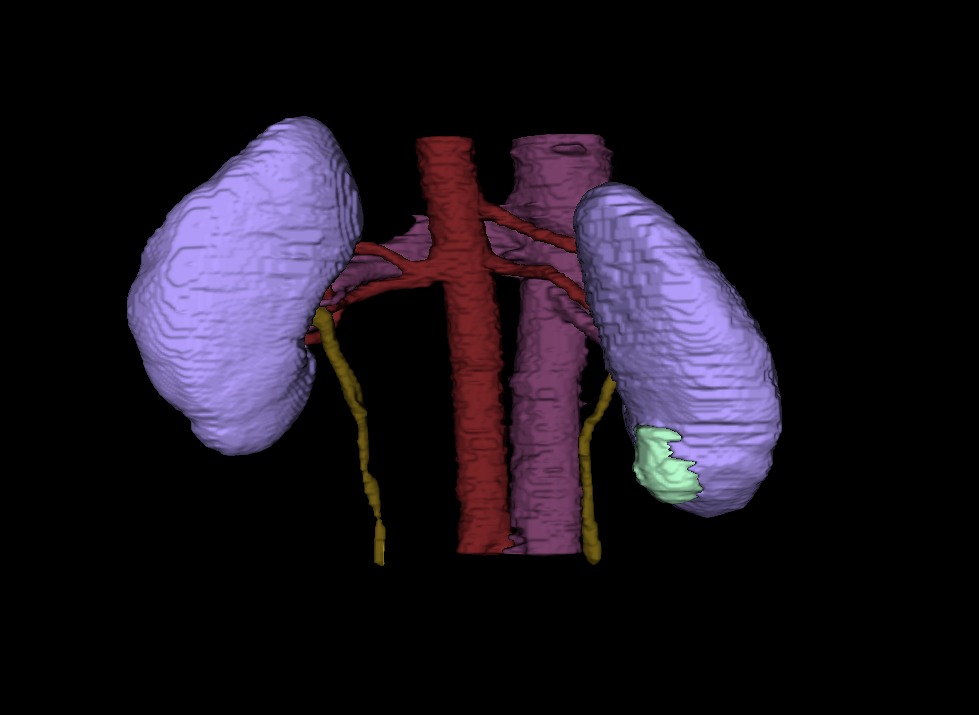

Heller is a PhD student conducting computer science research at University of Minnesota. His research focuses on using computer technology to enhance medical imaging, like a CT scan or an MRI. According to Heller, the magnified images will allow radiologists to quantify the type of tumor it is, saving time between a patient’s diagnoses and treatment.

“They will be able to measure a tumor mass, determine how big and rough they are, and whether they look distinct or blurry against the background. Medical professionals can use that information to choose the most effective treatment and predict a patient's outcome,” Heller explains.

“Then we can turn those numbers into a computer code. If we can automate the code with images and equipment, a radiologist can just hit a button and receive information on the tumor, rather than looking at the image and making a judgement call,” Heller states.

Eventually, Heller hopes using data driven decisions will create useful tools for radiologists and aid in the discovery of visual biomarkers for non-invasive kidney cancer. Most importantly, the computer algorithms would help medical professionals become more effective in treating the disease and allow scientists to conduct more research based off the numerical patterns they see in each stage of the disease.

(Courtesy: Nick Heller)